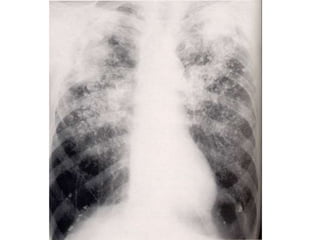

Patrón alveolar difuso EDEMA

PULMONAR

PULMONAR(Distress)